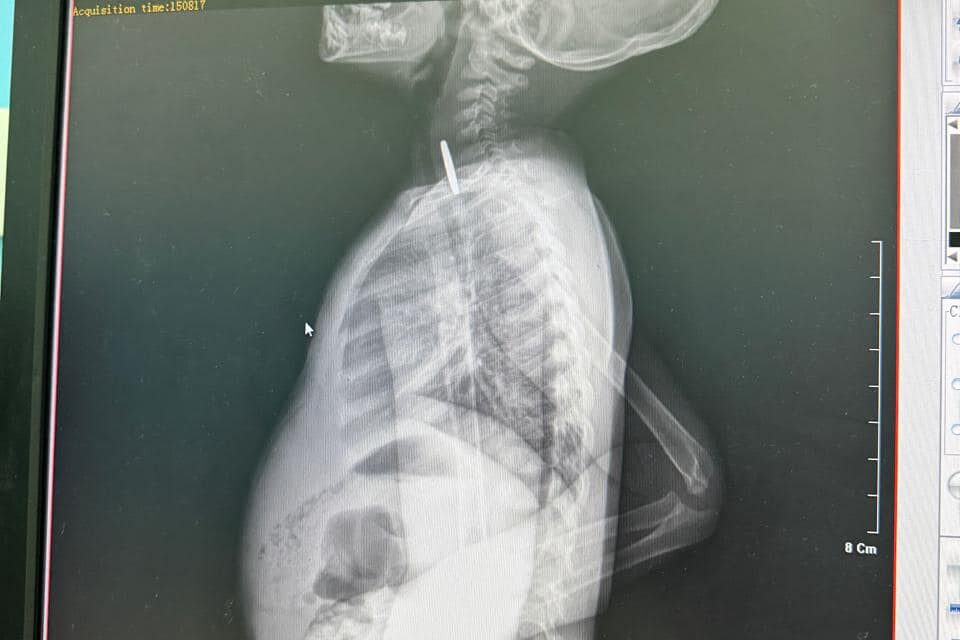

Os profissionais de saúde do Hospital Geral da Lunda-Sul realizaram com sucesso uma intervenção que permitiu retirar uma moeda metálica encravada na garganta de uma criança de seis anos.

Segundo o director da unidade hospitalar, Joel Wanga Upale, o menor deu entrada em estado de risco, tendo sido prontamente assistido pela equipa médica de serviço. A intervenção decorreu sem complicações, possibilitando a remoção do corpo estranho e a estabilização do paciente, salvaguardando-lhe a vida.

De acordo com a direcção do hospital, a criança encontra-se fora de perigo e permanece sob observação médica, devendo receber alta nas próximas horas.